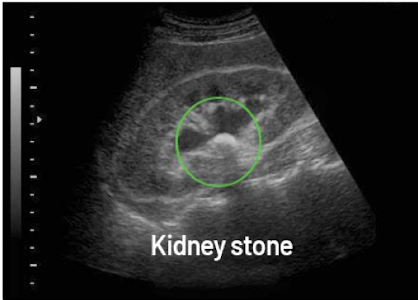

What is this and what type of scan

Renal Calculi, US